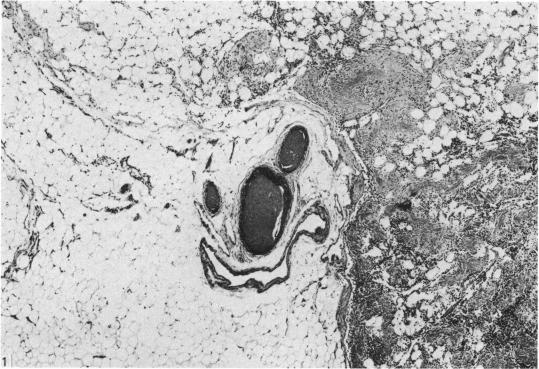

Injection of the arterial tree supplying human inguinal (superficial) and mesenteric (deep) lymph nodes was performed using a barium sulphate suspension. Radiography and histological examination showed two distinct types of arterial supply to lymph nodes. The superficial inguinal nodes are generally supplied by a single artery which penetrates the hilum and then radiates outwards to the lymph node pulp. The deep mesenteric lymph nodes, in contrast, are invariably supplied by several separate arteries which penetrate the nodal capsule, enter the trabeculae and run centripetally. These differences reflect the microanatomical differences in structure between deep and superficial lymph nodes. The two types of blood supply may be responsible for the different patterns of ischaemia found in deep and superficial lymph nodes. The findings re-emphasise the heterogeneous character of lymph nodes in man.

使用硫酸钡混悬液对供应人类腹股沟(浅表)和肠系膜(深部)淋巴结的动脉树进行注射。放射照相和组织学检查显示,淋巴结有两种不同类型的动脉供应。腹股沟浅淋巴结一般由一条动脉供应,该动脉穿透淋巴结门,然后向外辐射至淋巴结髓质。相比之下,肠系膜深淋巴结总是由几条独立的动脉供应,这些动脉穿透淋巴结被膜,进入小梁并向心性走行。这些差异反映了深部和浅表淋巴结在结构上的微观解剖差异。这两种血液供应方式可能是导致深部和浅表淋巴结缺血模式不同的原因。这些发现再次强调了人类淋巴结的异质性。